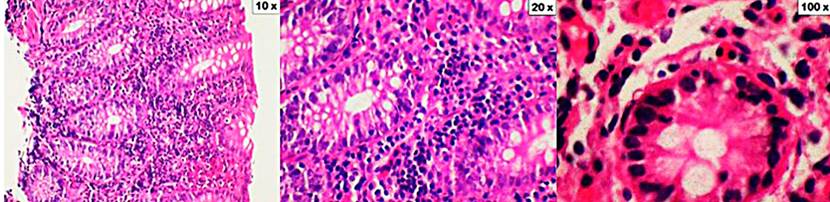

Figura 2 CL. Los cortes muestran la mucosa del colon distorsionada por un importante aumento de linfocitos intraepiteliales (aumento de 10x). En la lámina propia hay un denso infiltrado inflamatorio constituido por linfocitos, células plasmáticas, eosinófilos y neutrófilos ocasionales (aumento de 20x y 100x). Coloración de hematoxilina y eosina (H&E).

En el período de 22 meses comprendido entre febrero de 2018 y noviembre de 2019, se realizó en nuestra institución un total de 2849 colonoscopias por diferente diagnóstico. En 116 casos la indicación fue diarrea crónica, en todos los casos se tomaron biopsias y se contó con el informe histopatológico, con lo que se encontró un total de 15 pacientes con diagnóstico de CM (Figura 1), dado por el hallazgo de infiltración de linfocitos en la lámina propia, o por el engrosamiento de la capa de colágeno. De acuerdo con los criterios histológicos, se encontró algún tipo de colitis microscópica en el 12,9 % de los pacientes a quienes se les tomó biopsia por diarrea crónica (Figuras 2 y 3).